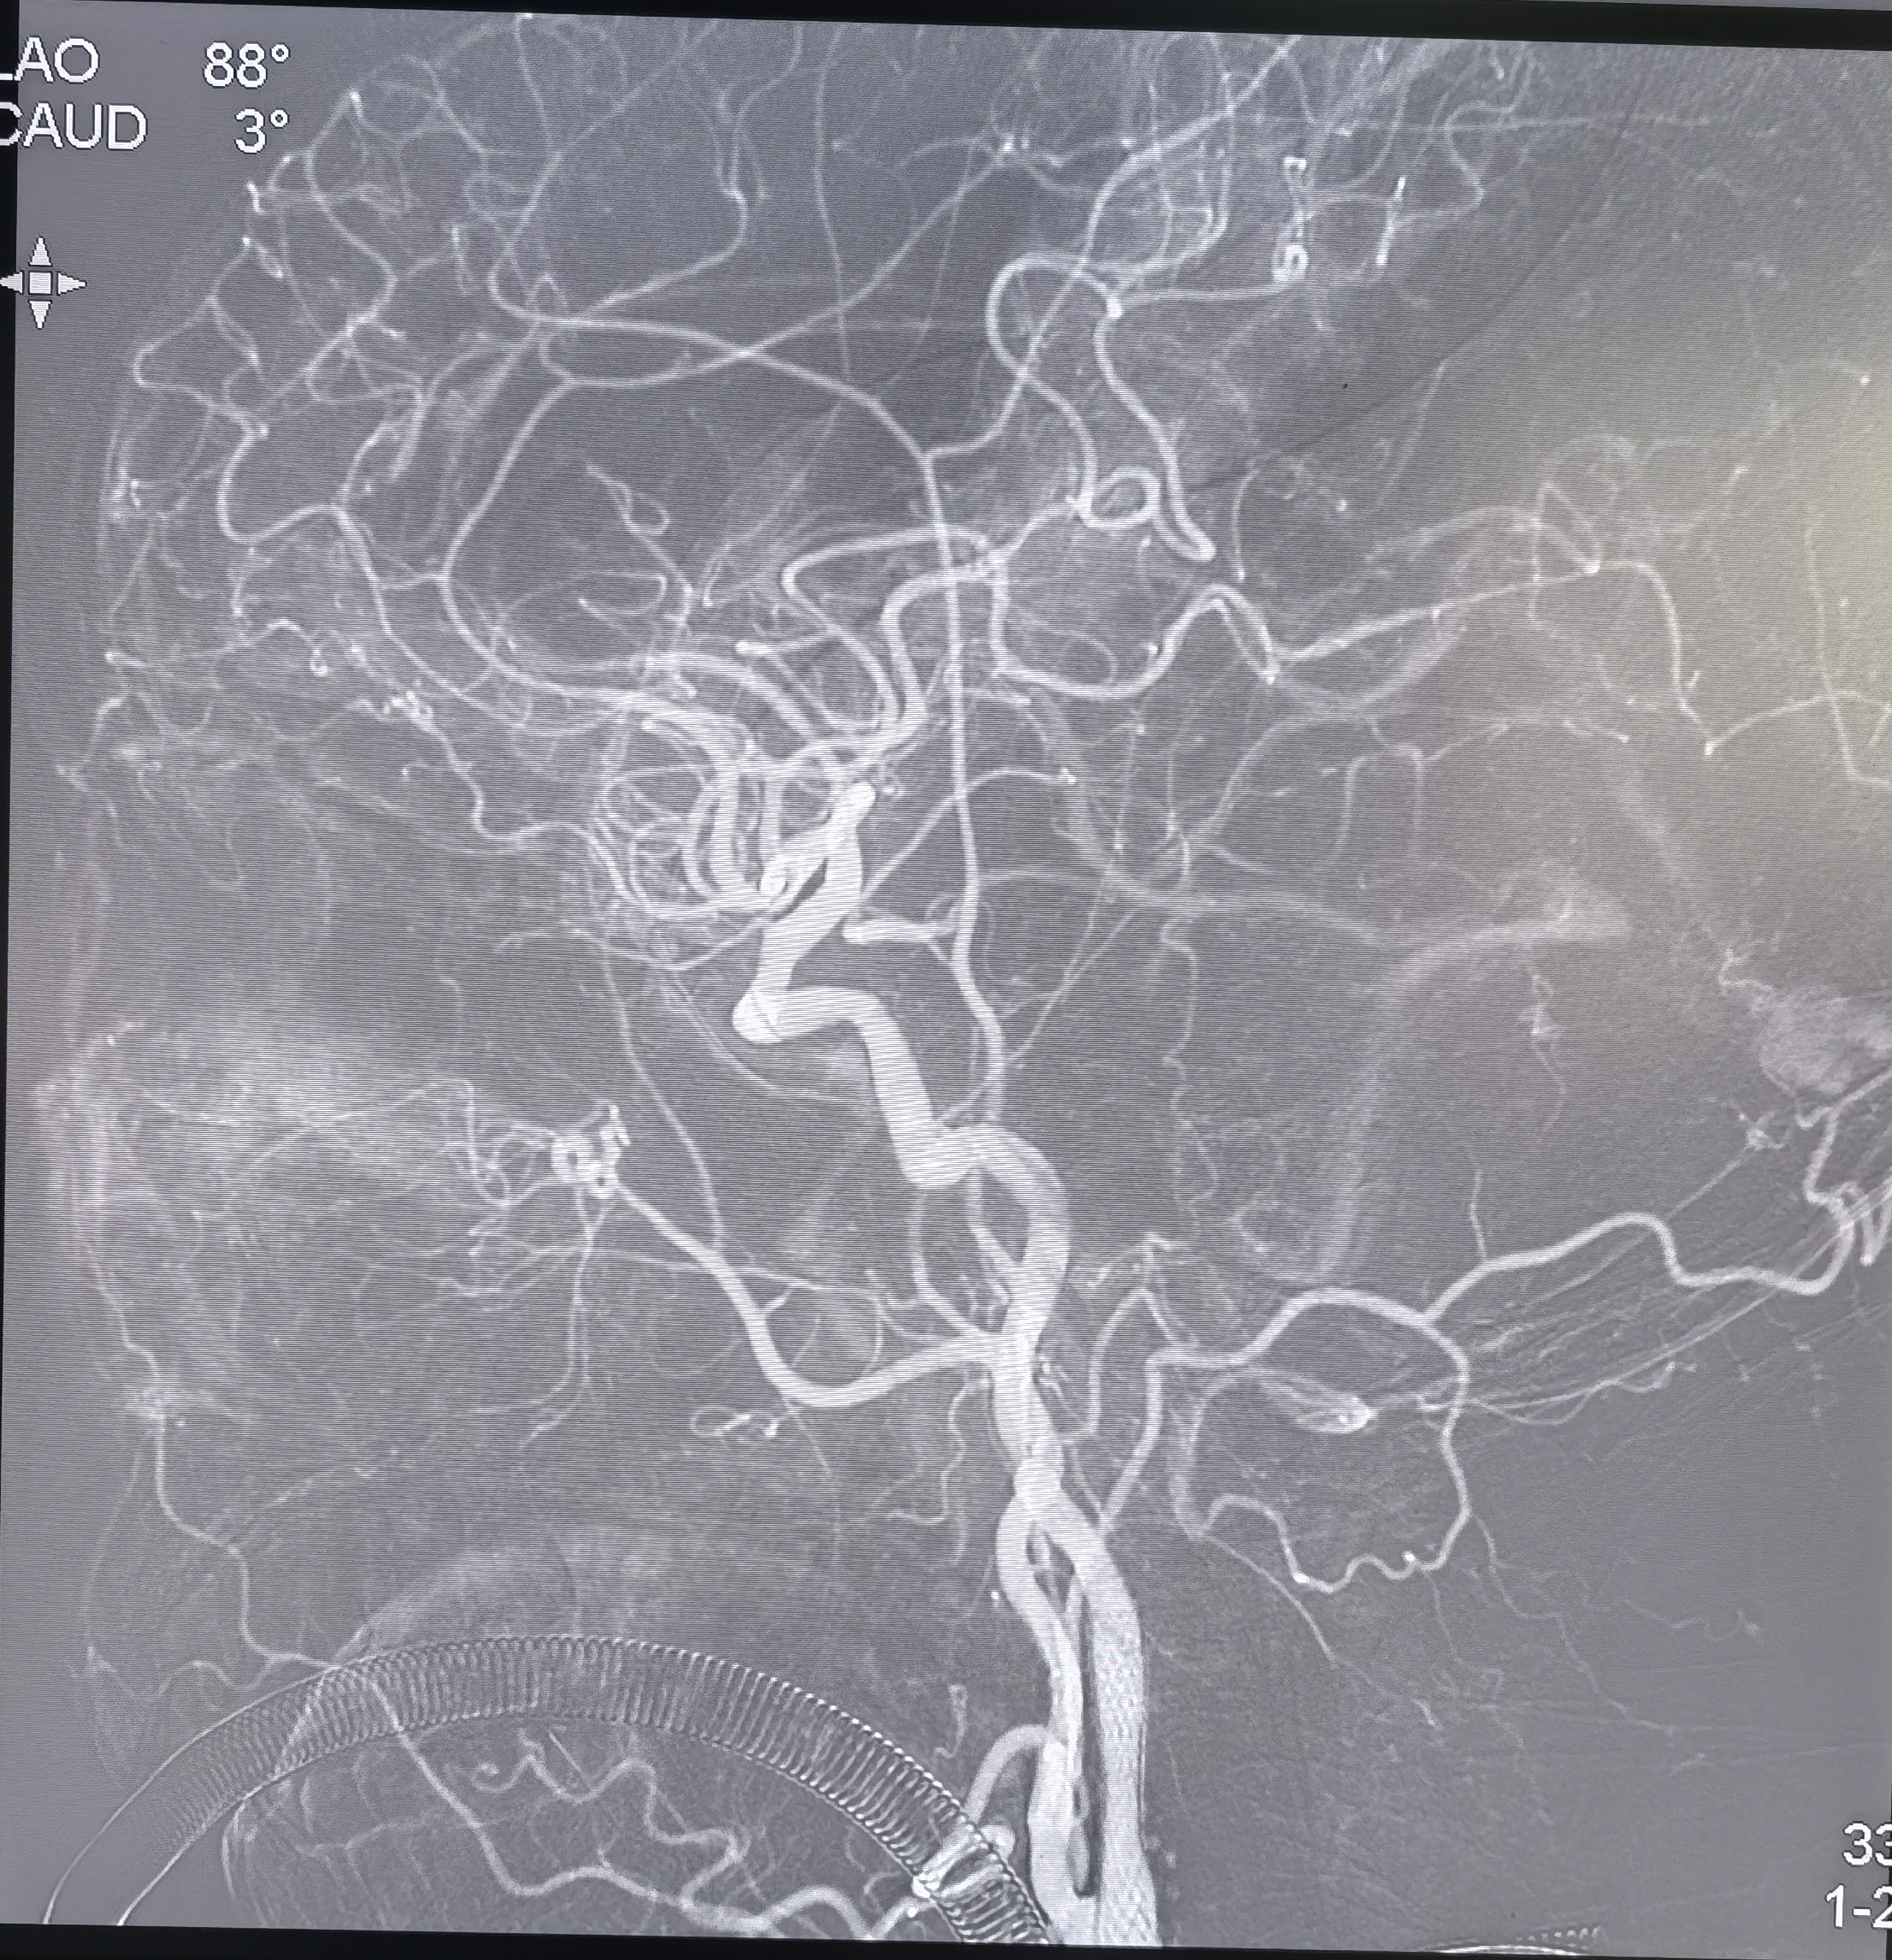

右侧椎动脉向左侧前循环代偿。

LICA闭塞急诊取栓、ICA起始段球囊扩张+支架置入、LVA起始段支架置入术